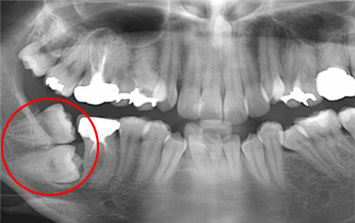

사랑니가 잇몸 속에 누워 인접치아가 깨지고 충치가 발생하여 심한 통증으로 내원한 환자